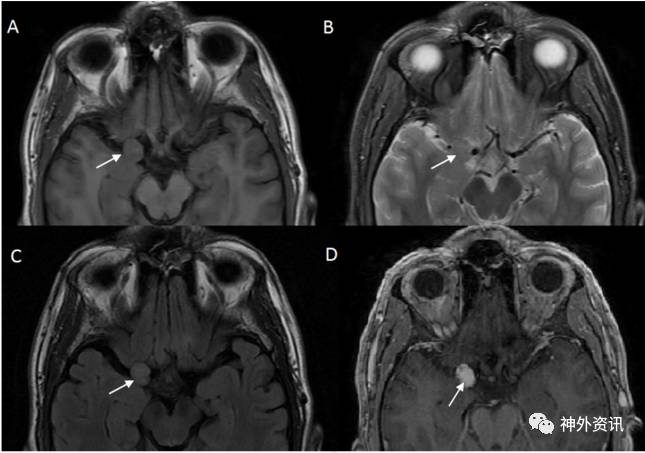

36岁男性患者。因外伤后行影像学检查,意外发现右侧中颅窝占位病变,无临床症状。术前MRI检查显示,右侧前床突一起源于硬脑膜的肿物,T1加权呈低信号,T2加权呈等信号,增强扫描均匀强化,考虑为脑膜瘤。经右侧翼点入路全切除病灶,无术后并发症。术后病理学检查,见病变为扩张、硬化的血管团,间质无神经组织,血管内有血栓形成,符合海绵状血管瘤。

图1. MRI轴位成像显示右侧前床突上方一起源于硬脑膜的占位病变(白色箭头)。A图为T1加权相;B图为T2加权相;C图为T2-FLAIR相;D图为T1加权相增强。